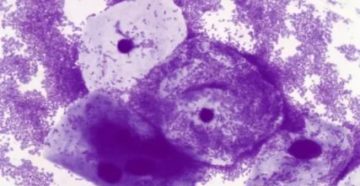

Коккобациллы в мазке при беременности Коккобацилярная флора в мазке может быть вариантом нормы или сигнализировать…